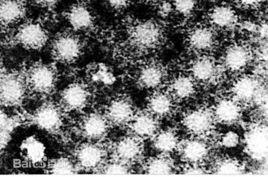

A型肝炎病毒(hepatitis A virus,HAV)為一直徑為27~32nm的二十面體立體對稱圓球形顆粒,無包膜,核心為單鏈正股RNA。HAV屬小RNA病毒科嗜肝病毒屬(hepatovirus)或嗜肝RNA病毒屬(heparnavirus)。HAV主要通過手-口途徑傳播,潛伏期15~50天,平均28天。病毒常在患者血清ALT升高前的5~6天就存在於患者的血液和糞便中。發病2~3周后,隨血清中特異抗體的產生,血清和糞便的傳染性就逐漸消失。HAV的實驗室診斷可進行抗體檢測。臨床上用的最多的是用ELISA方法查A型肝炎抗體抗體。